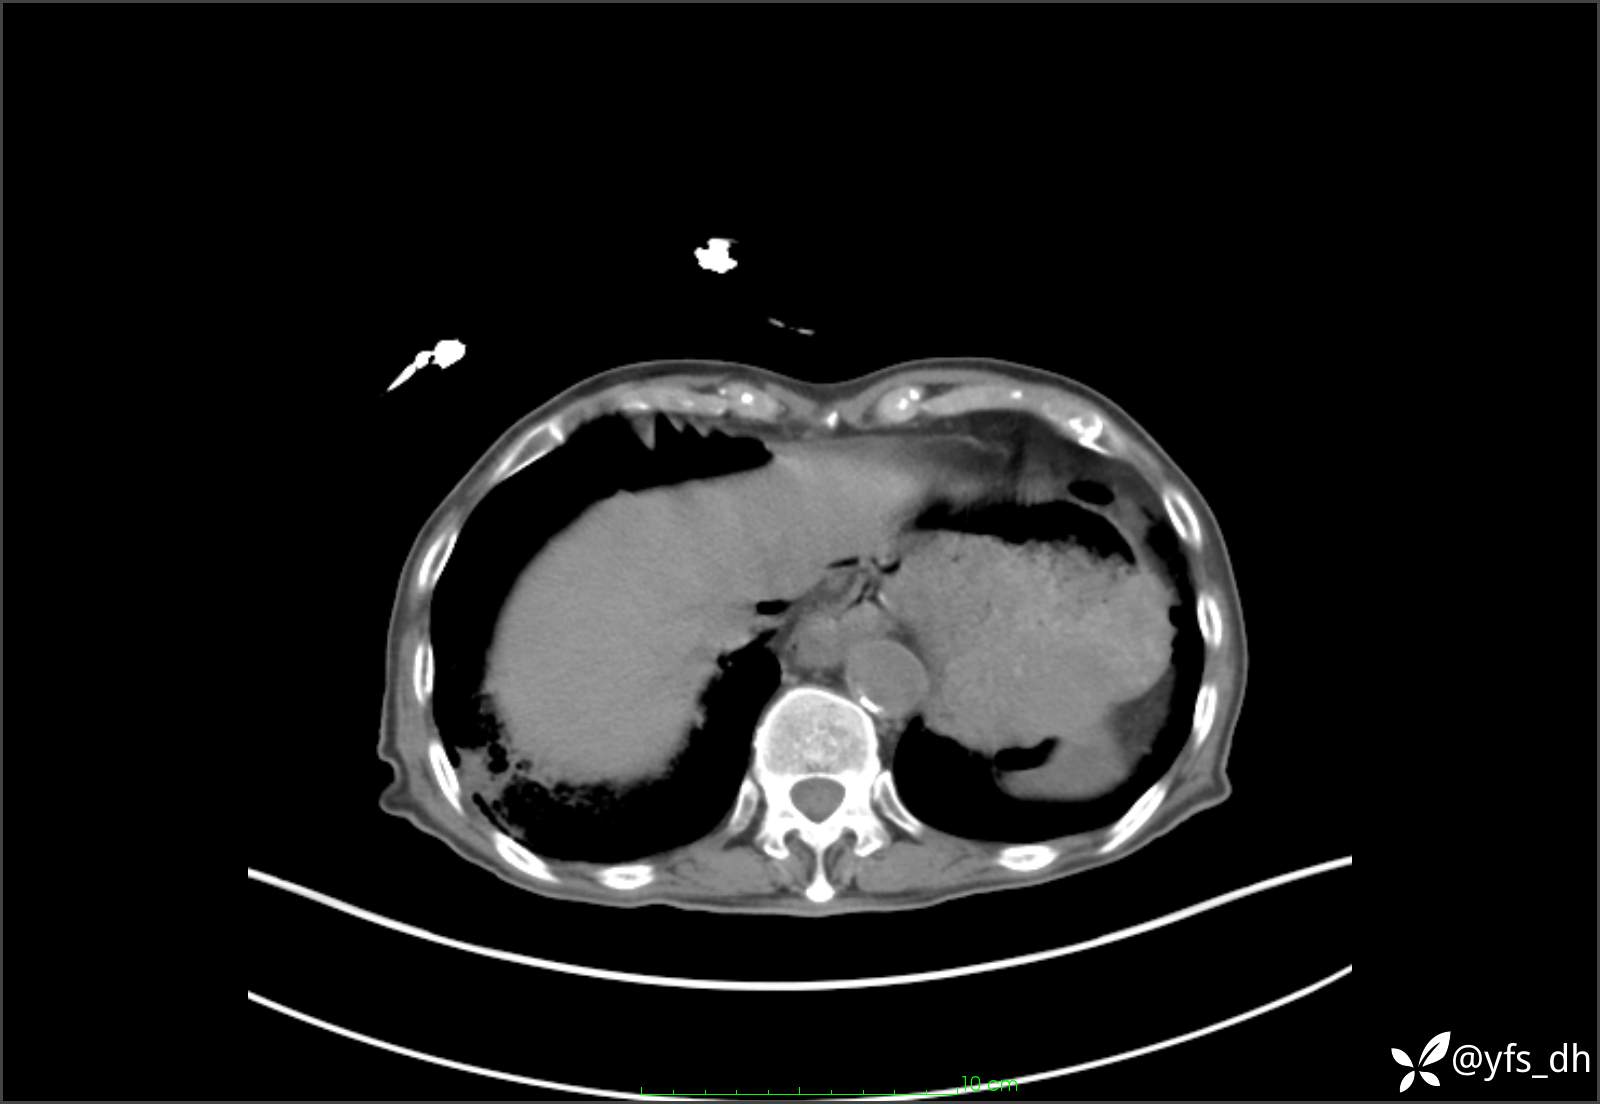

1.简要病史:患者4天前突发上腹部疼痛不适,但可以忍受。3小时前饭后突然加重,不能忍受后就诊。

2.简要手术记录:术中见腹盆腔大量肠液及粪便,乙状结肠中下段见一约3cm的破口。